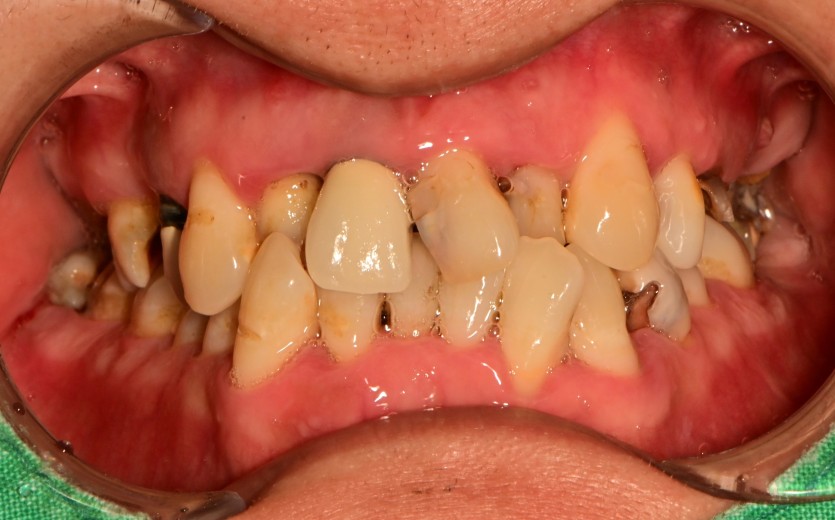

상악 전체 임플란트 증례입니다.

10개의 임플란트로 완성하였습니다.